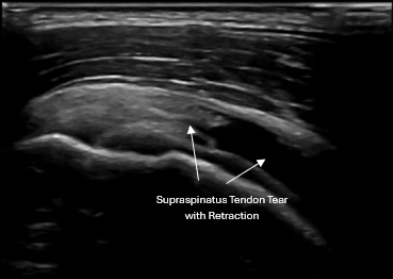

• Shoulder pain & rotator cuff injuries

Musculoskeletal Ultrasound evaluating rotator cuff injury in active adult

• Identify tendon tears, tendinopathy, and inflammation